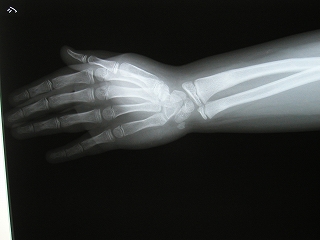

‰E‘O˜rœœÜ

@@”N—î@@8Î@—«

@@•‰“ú@•½¬14”N7ŒŽ27“ú

œÜÇ—á